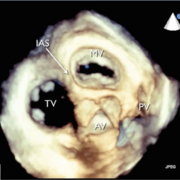

We are investigating the differences that exist between normal and abnormal cardiac valves, specifically by using echocardiographic data to describe valvular morphology and dynamism over the cardiac cycle both qualitatively and quantitatively

One of our current focuses is a tricuspid annular analysis. We are examining the structural changes of the tricuspid annulus over the cardiac cycle. Our current methodology is being applied to both normal and abnormal annuli. We have also demonstrated the ability to prototype patient-specific annuli using CAD software and 3D printing.

Khurram Owais, MD, Charles E. Taylor, PhD, Luyang Jiang, MD, Kamal Khabbaz, MD, Mario Montealegre-Gallegos, MD, Robina Matyal, MD, Joseph H. Gorman III, MD, Robert C, Gorman, MD, Feroze Mahmood, MD. Tricuspid Annulus: A Three-Dimensional Deconstruction and Reconstruction. Ann Thorac Surg. 2014; 98:1536-43)